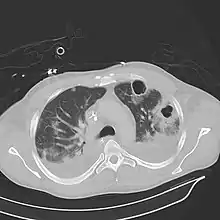

Computed tomography (CT) scan of chest showing bilateral pneumonia with abscesses, effusions, and caverns. 37-year-old male. | |